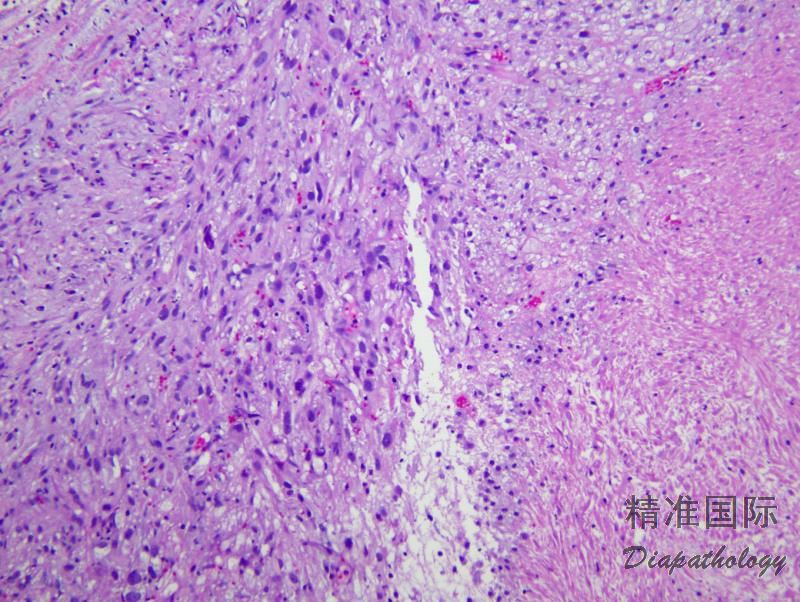

肿瘤由浸润性、交错排列的梭形细胞束组成,细胞核呈雪茄样,胞浆嗜酸性,可见核周空泡;

细胞可显示不同程度的异型性,细胞密度中-高,可见核分裂像及不典型核分裂像;

可见上皮样瘤细胞,偶尔可完全表现为上皮样特征;

可见黏液变性;

依据细胞异型性、核分裂计数以及坏死等特征,平滑肌肉瘤可分为低级别及高级别两级:

低级别者表现为细胞轻~中度异型,核分裂像<5 个/10HPF;

高级别平滑肌肉瘤有明显细胞异型性,多数病例核分裂像>5 个/10HPF;

大多数膀胱平滑肌肉瘤为中-高级别。